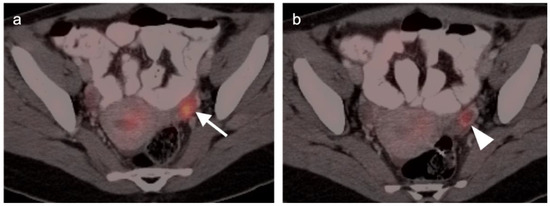

3.1. Prostate Cancer

3.2. Urothelial Carcinoma